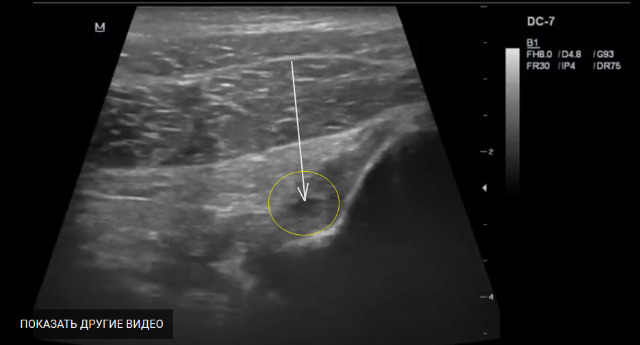

Поддержу Алексея,я за частичный разрыв.С учетом факта травмы я бы расценил как частичный разрыв (ЗКС).

Да и гадать здесь нечего, в данном случае частичный разрыв ЗКС и ПКС в проксимальной части.

Из видео четко видно, что обе связки резко утолщены и имеются несколько участко частичного разрыва.

ПКС: